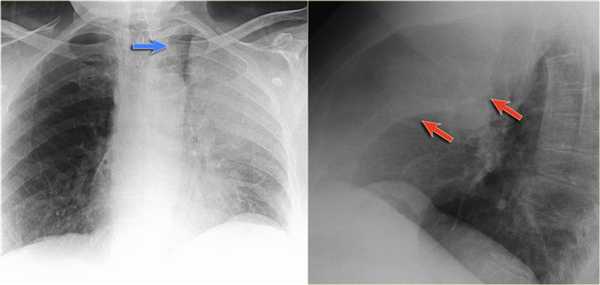

Ателектаз верхней доли правого легкого.

Оцените ниже лежащие изображения, а после продолжите чтение.

- Трехгранное затенение.

- Подъем правого корня легкого

- Облитерация загрудинного пространства (указано стрелкой).

На ПЭТ/КТ визуализируется опухоль легкого с обструкцией правого верхнедолевого бронха, как следствие ателектаз верхний доли правого легкого.

Также очень частым проявлением ателектаза является подъем диафрагмы, что хорошо визуализируется на ниже представленной рентгенограмме (указано синий стрелкой).

У данного пациента карцинома легкого с билатеральным метастазированием в легкие (указано красными стрелкам).